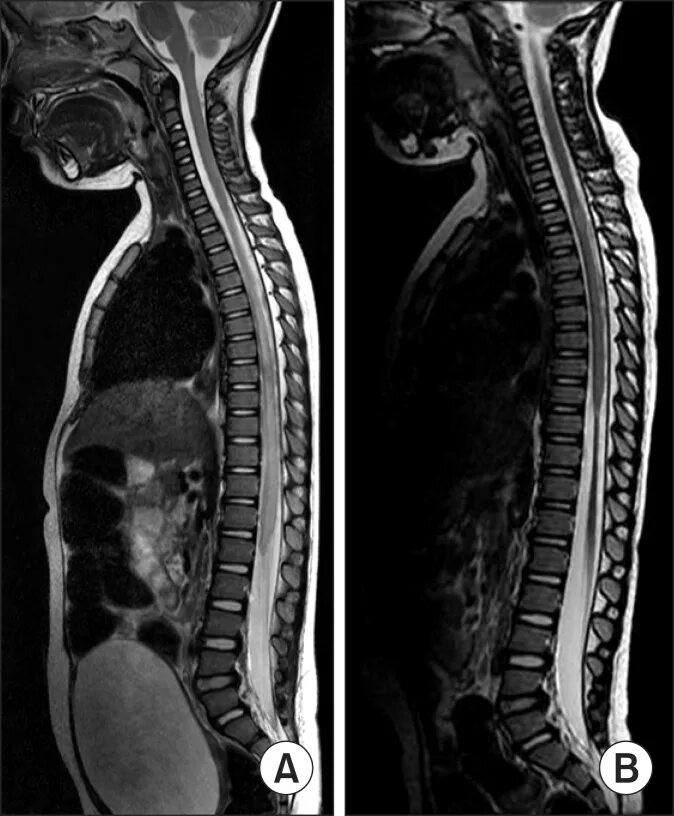

Spine mri